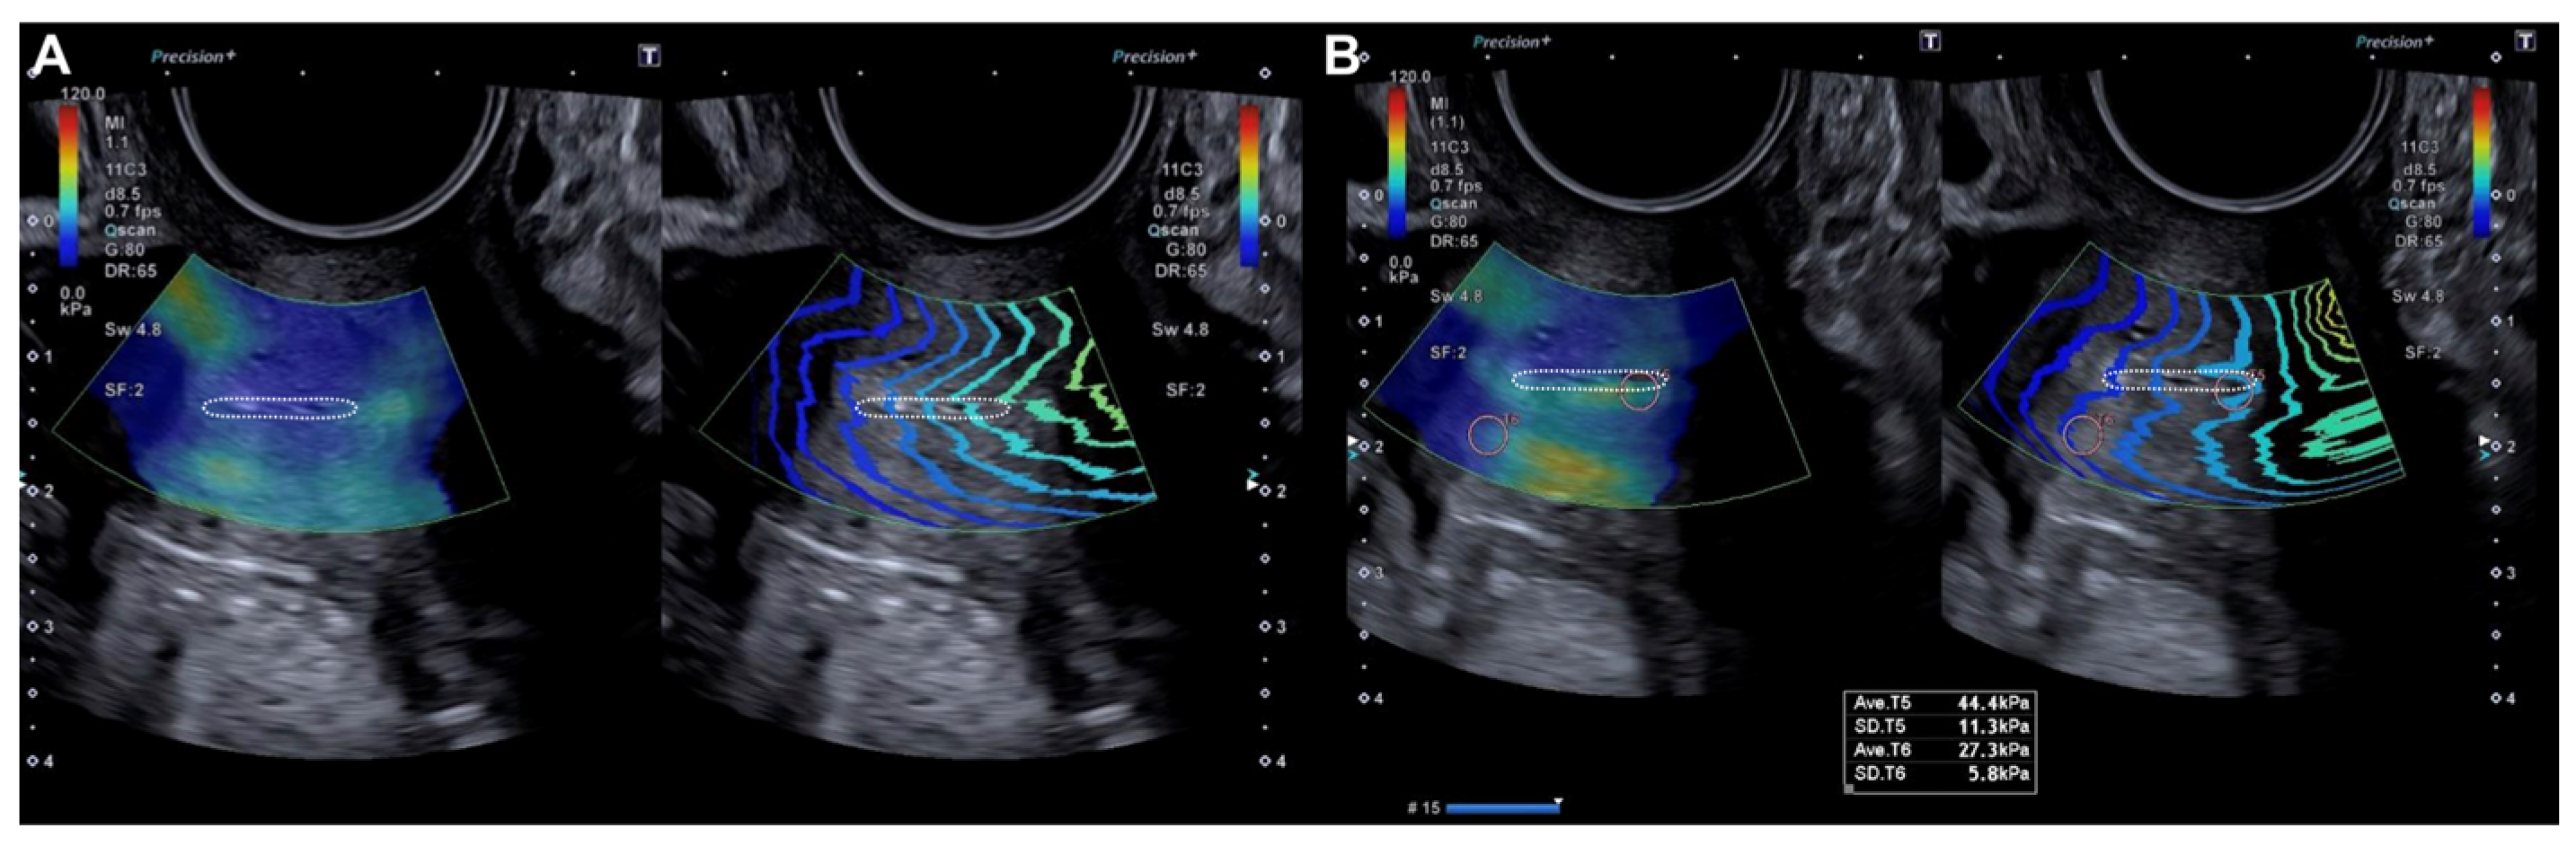

2.2.2. Evaluation Using SonoElastoColposcopy

- Sainz, J.A.; Castro, L.; Romo, J.M.; Holgado, A.; Fernández-Palacín, A.; García-Mejido, J.A. Evaluation of Pre-Malignant Lesions of the Uterine Cervix by Shear Wave Elastography: A New Diagnostic Tool. Ultrasound Med. Biol. 2021, 47, 3275–3282. [Google Scholar]

- Dudea-Simon, M.; Dudea, S.M.; Ciortea, R.; Malutan, A.; Mihu, D. Elastography of the uterine cervix in gynecology: Normal appearance, cervical intraepithelial neoplasia and cancer. A systematic review. Med. Ultrason. 2021, 23, 74–82. [Google Scholar] [CrossRef]

- Liu, C.; Li, T.T.; Hu, Z.; Li, Y.; Cheng, X.; Zhu, Y.; Lu, M. Transvaginal Real-Time Shear Wave Elastography in the Diagnosis of Cervical Disease. J. Ultrasound Med. 2019, 38, 3173–3181. [Google Scholar] [CrossRef]